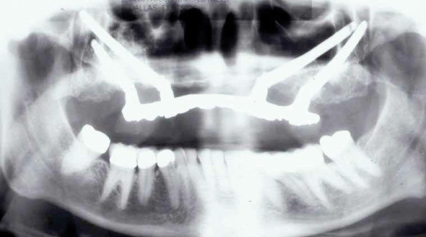

Fig 6. Panoramic radiograph of 56-year-old patient illustrating a number of dental procedures historically.

Figure 6

Interceptive implant therapy may then become a consideration earlier in life to create restorations that will not be subject to the latent effect of dental caries as aging continues. An example is shown in Figure 6 and Figure 7; the panoramic film of a 56-year-old man shows several orthognathic and extensive dental procedures historically. All full-coverage restorations had been replaced for a second time, and, again, all evidenced recurrent caries, but the existing dentition was periodontally sound and relatively esthetic.